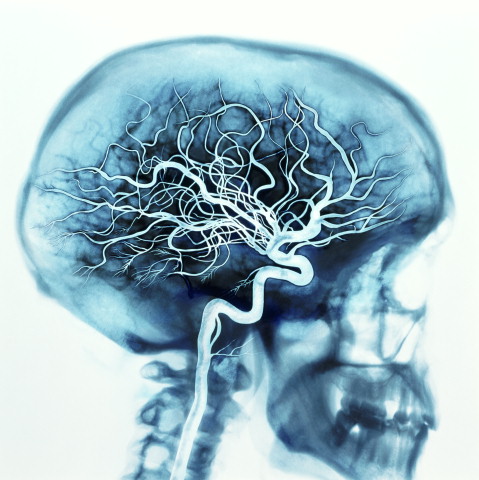

ENTER THE BRAIN